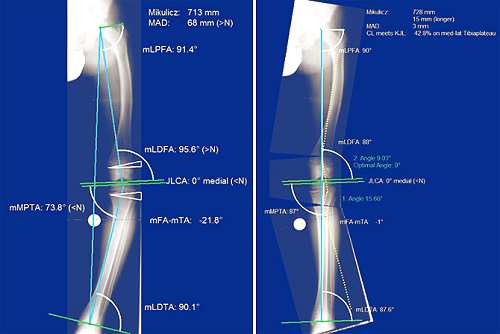

Chức năng giải phẫu xương được dùng để lập kế hoạch nắn chỉnh xương đùi hoặc xương chày, với các ca nắn xương đơn lẻ hoặc kết hợp nhiều phần, sử dụng kỹ thuật “chêm mở” hoặc “chêm đóng”.

Phần mềm MediCAD có chức năng tự động kiểm tra các sai lệch trục, bác sĩ có thể tự điều chỉnh hoặc sử dụng điều chỉnh tự động của phần mềm.

Sau khi bác sĩ xác định các tọa độ quan trọng trong hình xương, phần mềm tự động xác định các kích thước sau khi nhận dạng tự động các mốc liên quan bằng chức năng “Cắt xương tự động”.

Lập kế hoạch phẫu thuật cắt xương nhằm mục đích điều chỉnh góc nghiêng cơ học được xác định trước của sự thẳng hàng chân.

Phần mềm có thể sửa chữa các sai lệch trục bằng cách chỉ định các vết cắt có liên quan. Chức năng này cho phép mediCAD LONG LEG hỗ trợ lập kế hoạch trước phẫu thuật nhanh chóng và hiệu quả.

Kết quả cho thấy chức năng cắt xương “Autoplan” có độ tin cậy liên bộ cao, độ tin cậy cao giữa các bộ phận và mối tương quan với các thông số cụ thể trong kế hoạch giải phẫu.

Phần mềm lập kế hoạch phẫu thuật MediCAD được thử nghiệm phù hợp với nhu cầu thực tế và được khuyến nghị để phân tích dị tật và lập kế hoạch nắn xương.